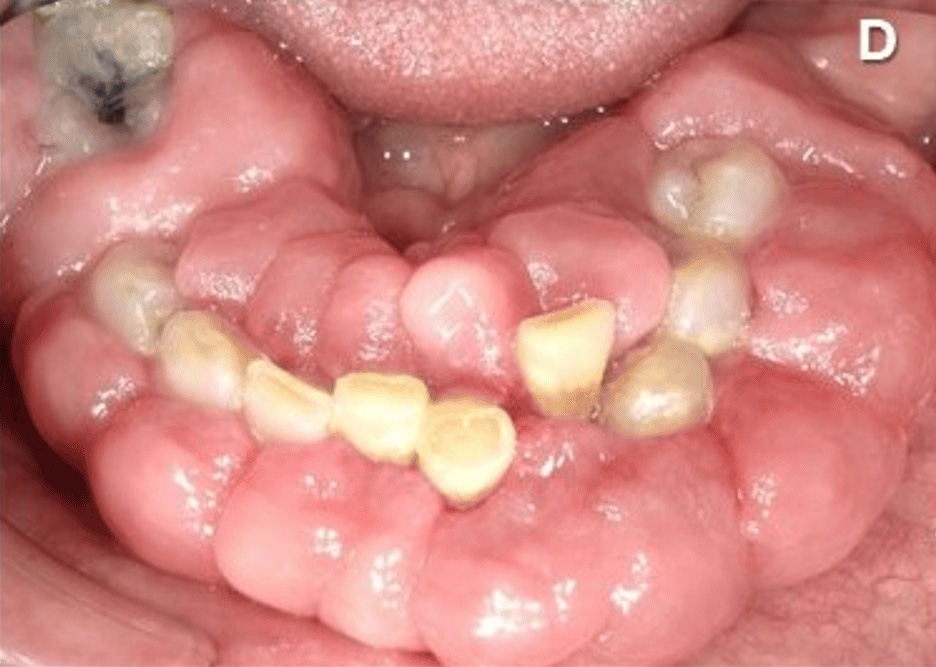

覚醒剤を乱用した61歳の男性の歯茎を撮影した画像。

5年間の覚醒剤使用とホームレス生活により口腔衛生不良があり、歯肉の肥大、疼痛、出血による咀嚼困難で病院へ。